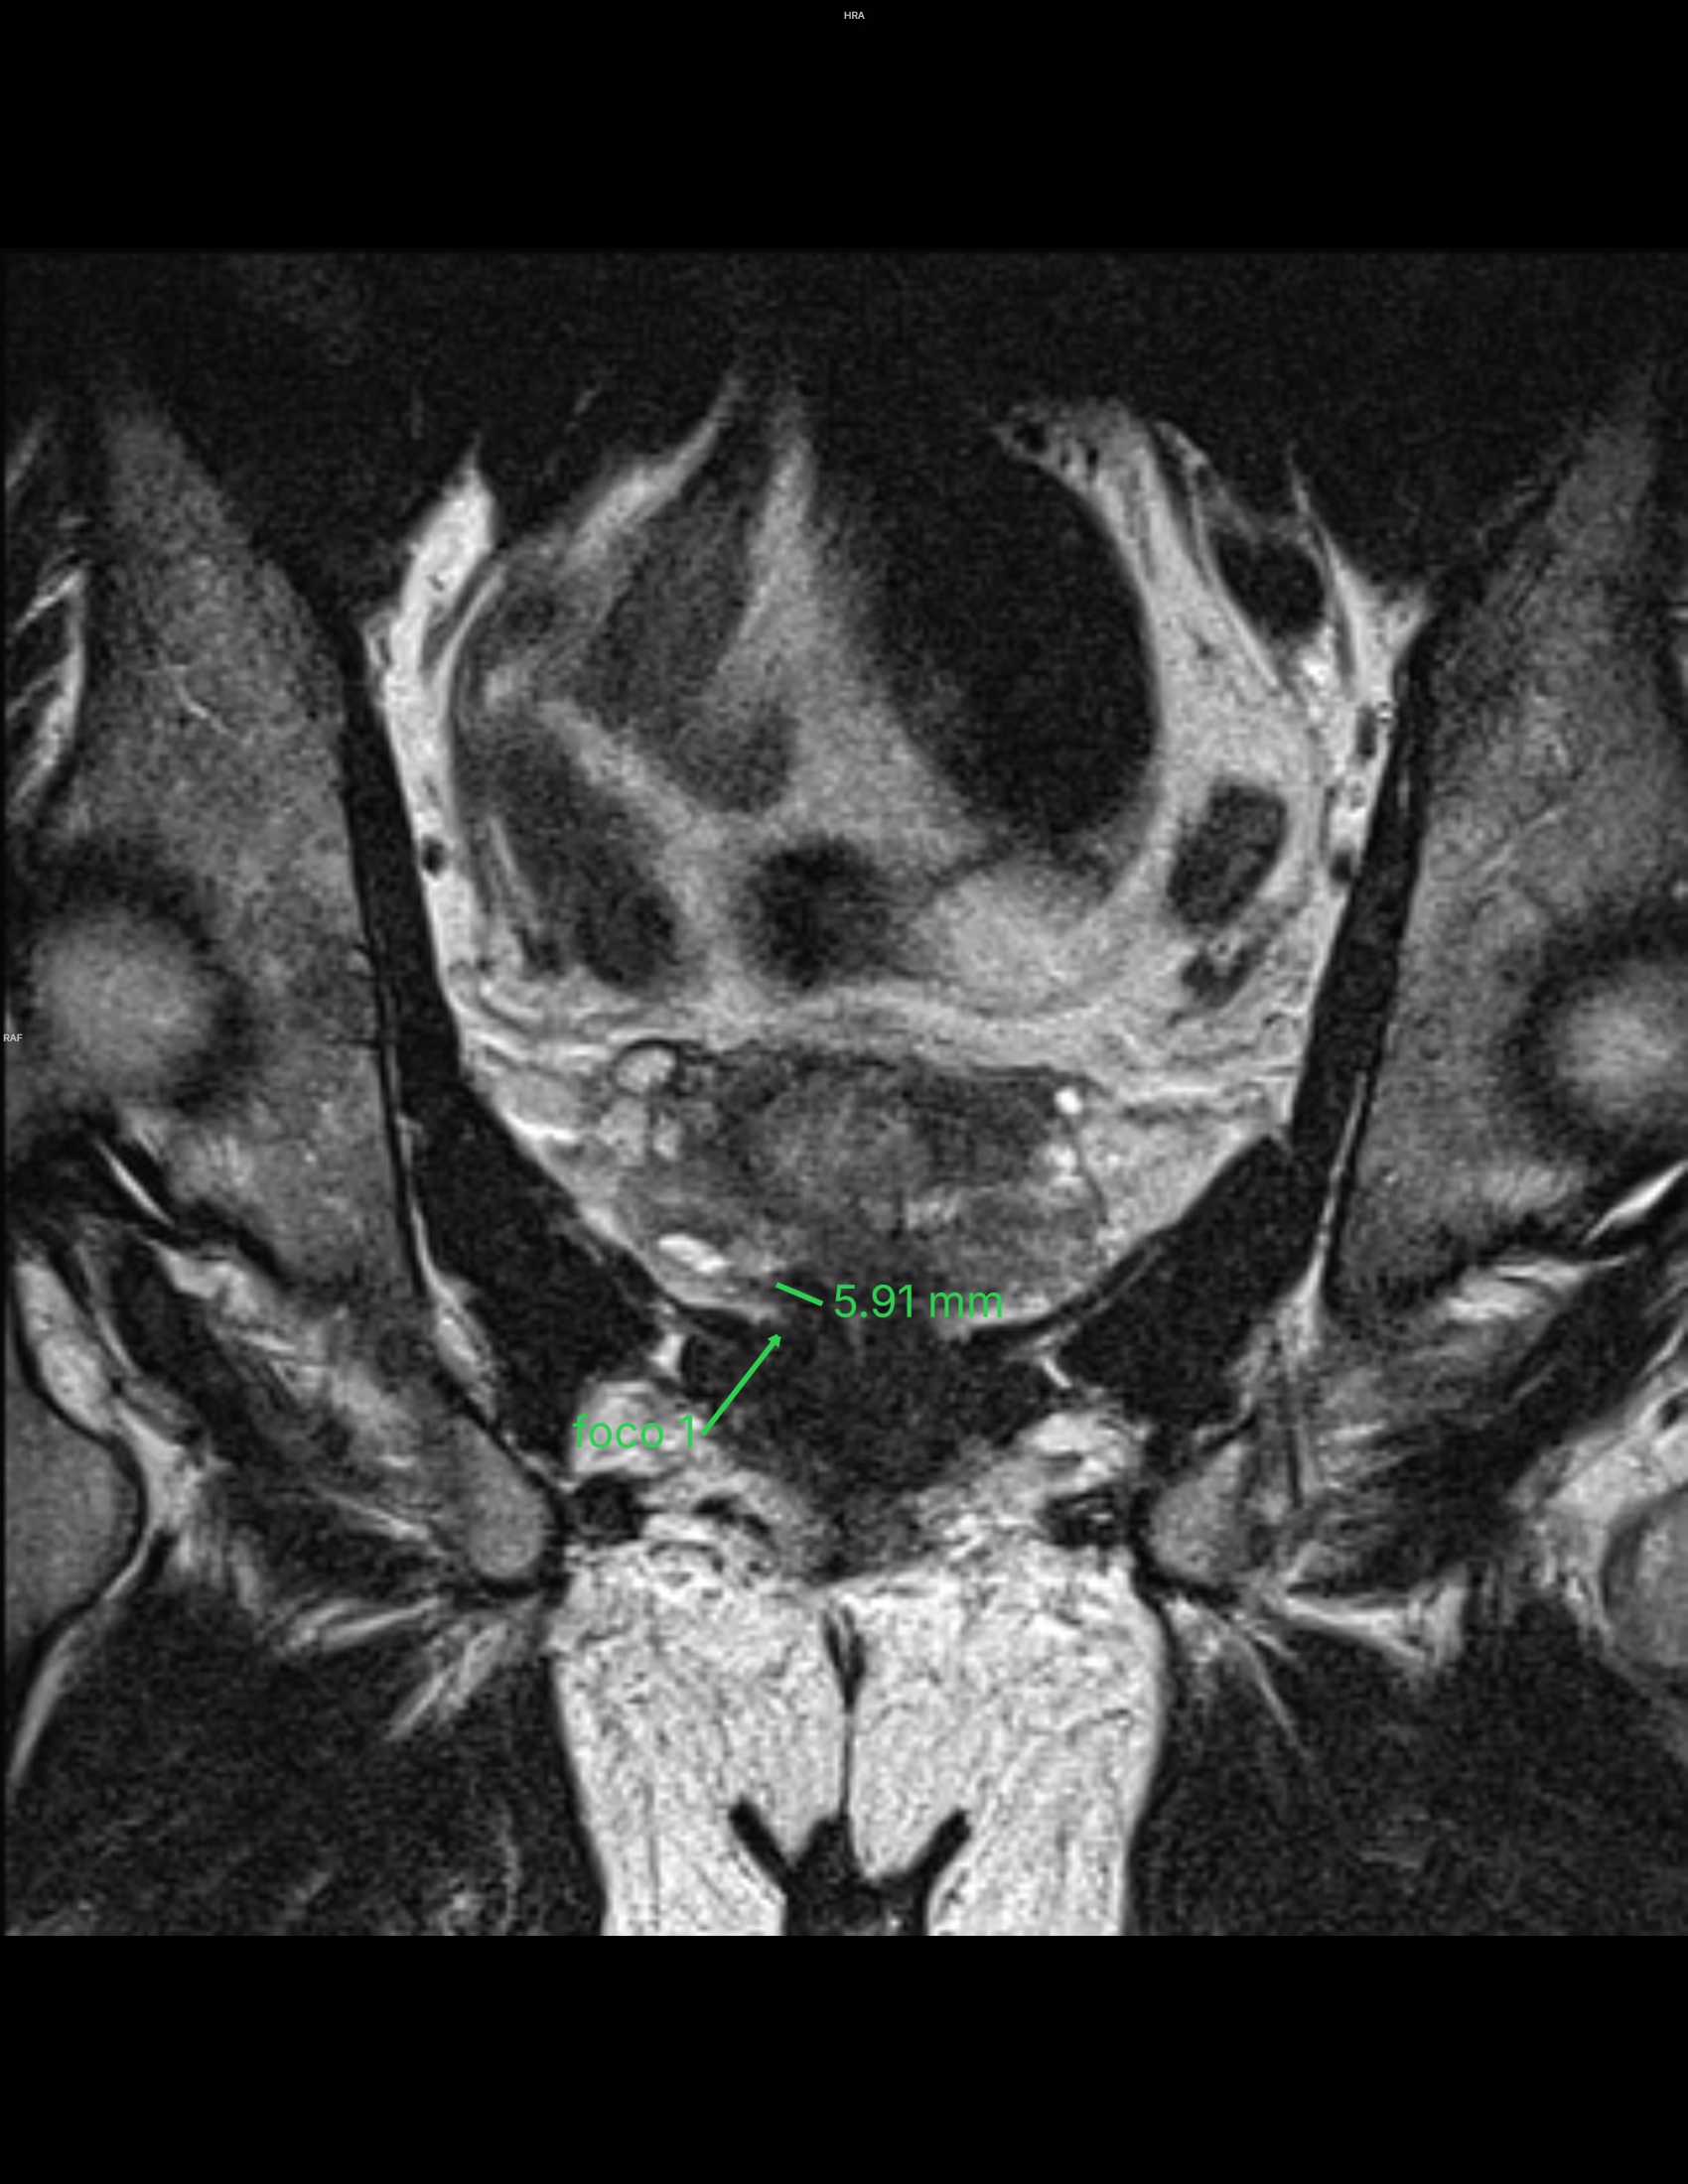

Lesión #1: Mide: aproximadamente 6 mm.

Serie 5, Imagen 22/30.

Localización: Zona periférica posteromedial derecha a nivel apical (sector RA-PZpm).

PEE: Probabilidad de Extensión extraprostática: grado 0 de 3 (Mehralivand).

T2: Hipointensidad menor a 15 mm y sin extensión extraprostática. Categoría 4/5.

DWI: Marcada hiperintensidad en difusión y marcada hipointensidad en ADC. Categoría 4/5.

PI-RADS 4

Lesión índice PI-RADS 4 en la zona periférica posteromedial derecha a nivel apical (sector RA-PZpm). Mide aproximadamente 6 mm, con probabilidad 0 de 3 de presentar extensión extraprostática